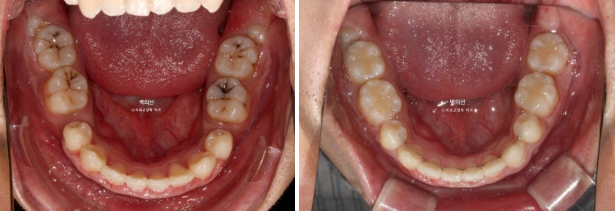

좌 - 치료 전 / 우 - 치료 후

23.07~25.05

이제 전후 비교 보겠습니다.

중심선은 잘 맞으며 과개교합은 좋아졌습니다.